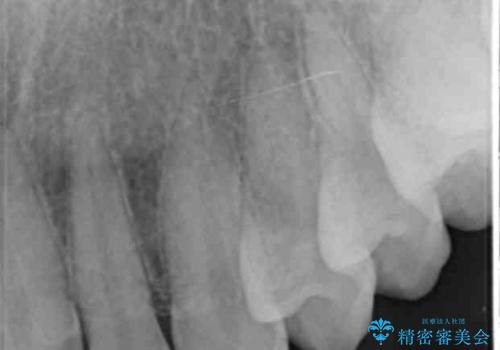

- 他院で昨年治療したセラミッククラウンが欠け、審美性の改善を求めて来院されました。

噛み合わせからクラウンが欠けやすい状態だったので、欠けにくく強度に優れるフルジルコニアクラウンで審美性を改善します。

フルジルコニアクラウンは若干透明感に劣る反面、強度に優れ大きな力のかかる部位に有効な補綴方法です。